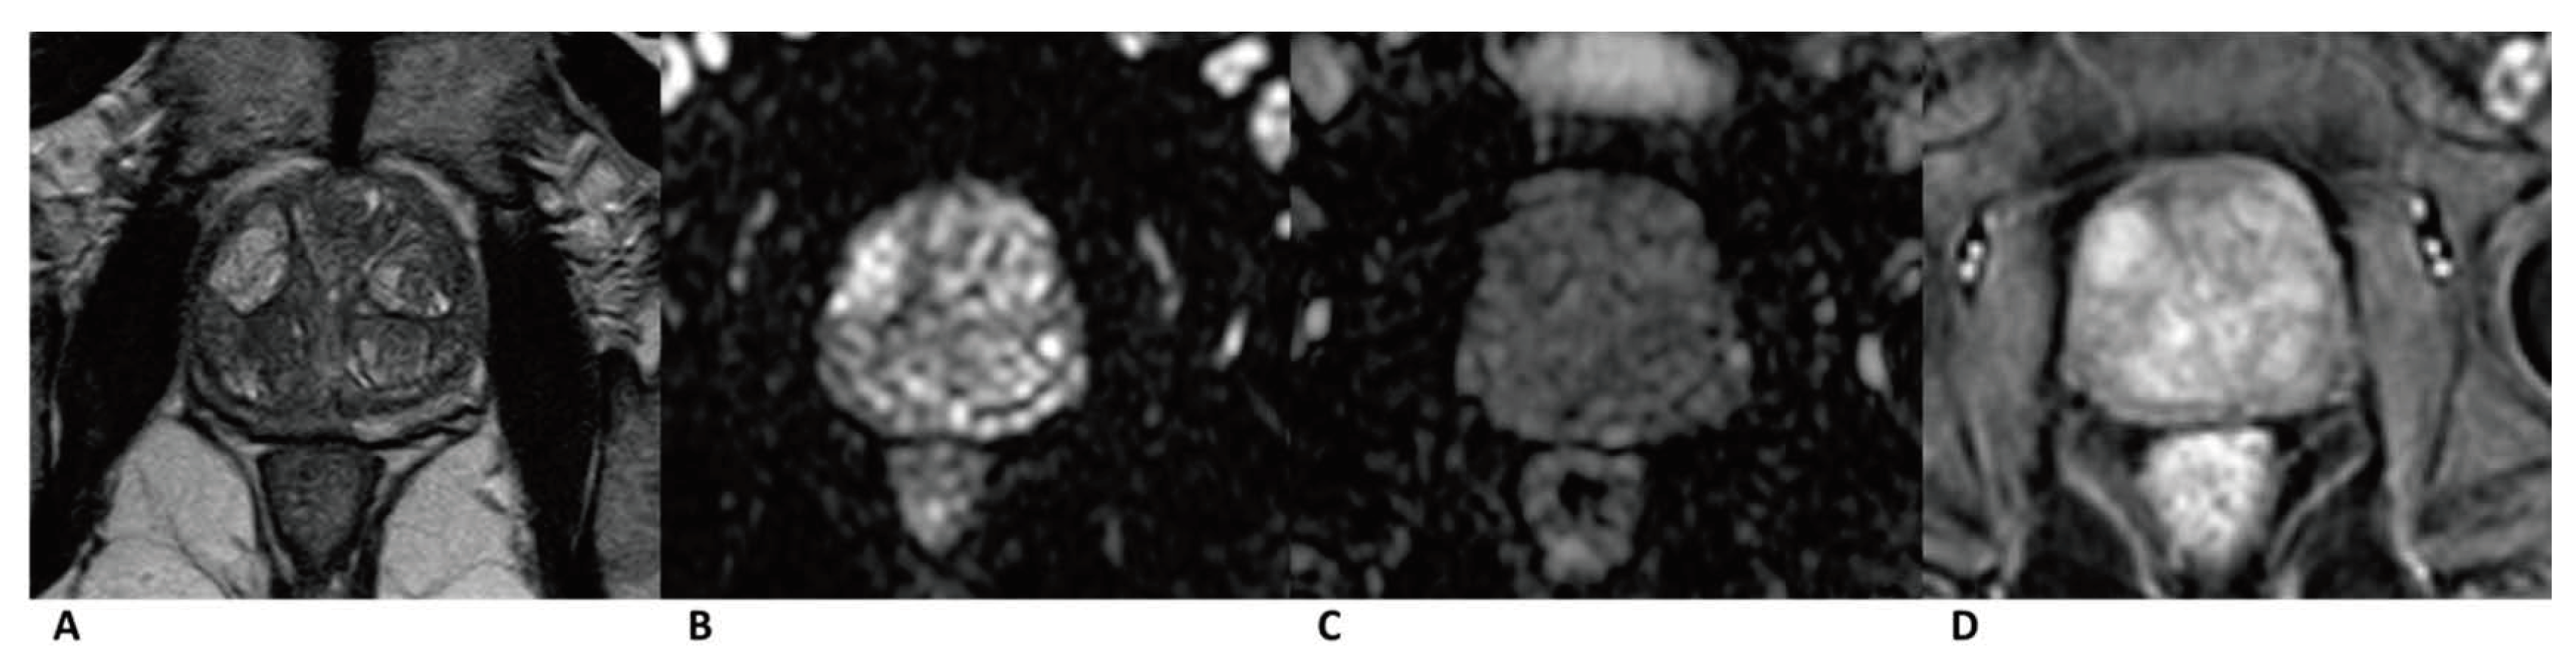

Figure 2. Case of prostate cancer in PZ. Male, 64 years old, prostate cancer with its longest diameter being >1.5 cm. T2WI showed a hypointense nodule in the left PZ (arrow) (A). The lesion was hyperintense on DWI (b = 1500 s/mm2) (arrow) and hypointense on the ADC images (B,C). Positive enhancement was seen on the DCE (arrow) (D). This lesion was finally assessed as a PI-RADS category 5, indicating that it had a high cancer risk according to PI-RADS v2, PA PI-RADS v2, and biparametric MRI protocols.